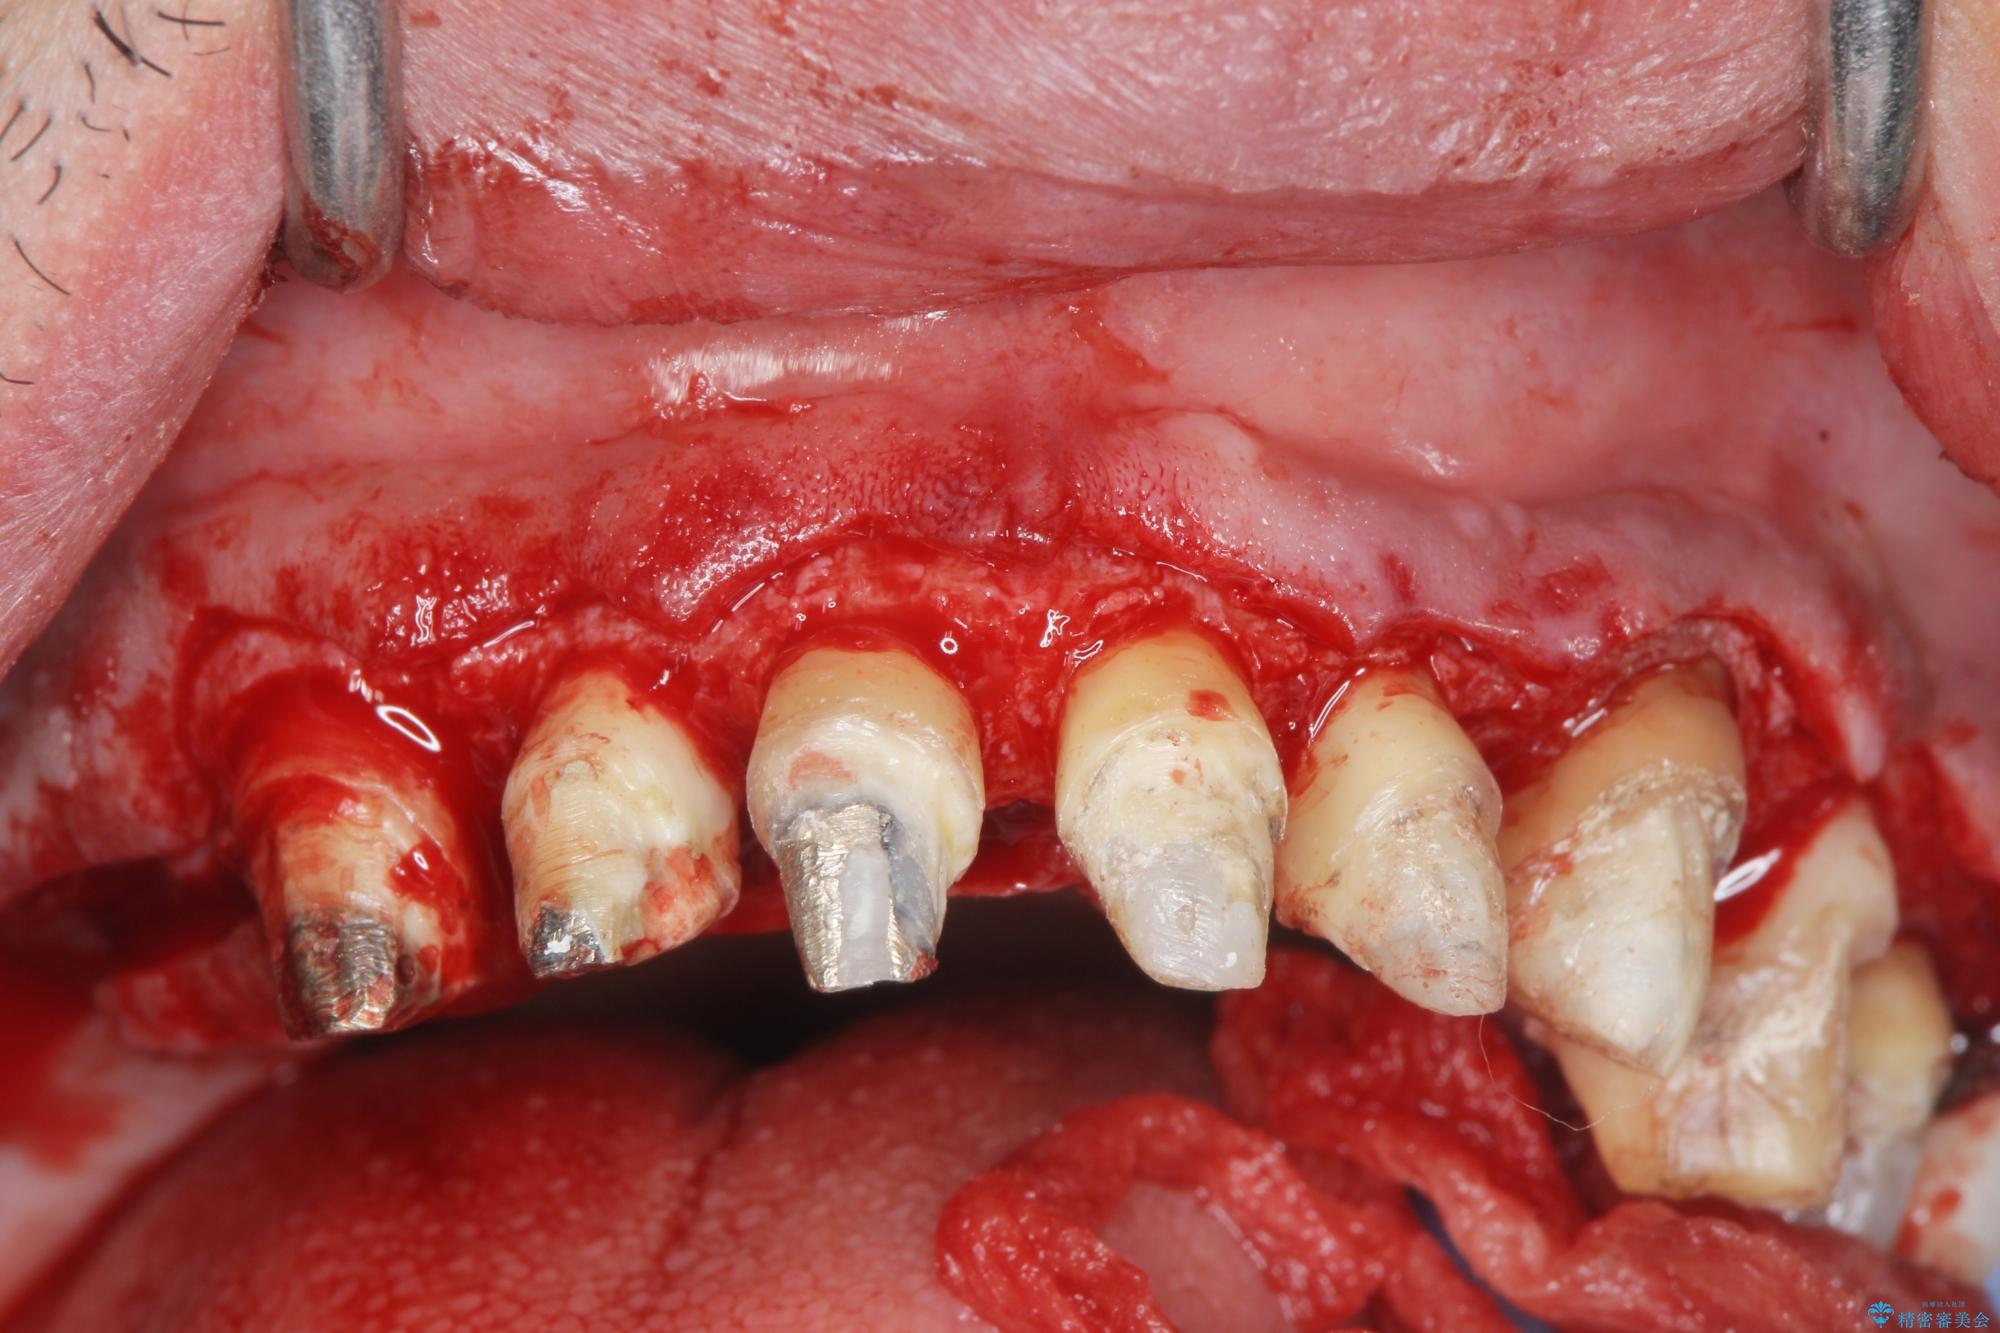

歯周組織検査を行うと歯ぐきからは容易に出血し、X線検査より歯とセラミッククラウンの適合が悪い(ピッタリと合っていない)状態が示唆され、歯ぐきの炎症を惹起している状態でした。

セラミッククラウンを除去し仮歯を装着し、歯周外科手術を行い歯ぐきの状態を改善したのち、適合の良いセラミッククラウンを再作製をする治療計画としました。